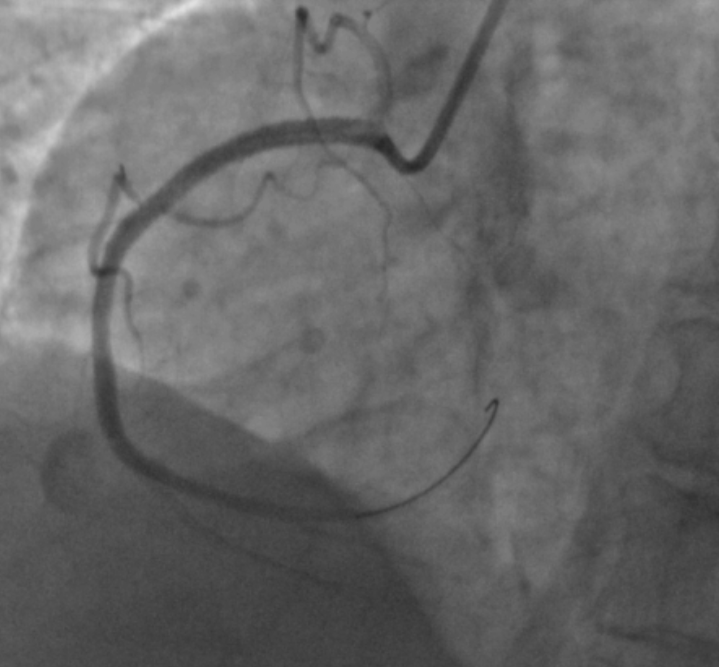

支架术后右冠血流通畅。通讯员供图

经检查,医生判断患者情况比较危急,需要紧急介入治疗开通血管,必要时还需要置入支架。家属和病人听闻后,有些犹豫不决,认为这么大年纪了,没必要做心脏支架手术。基于患者身体情况还不错,没有太多基础疾病,冠脉造影也仅是显示右冠闭塞,左侧冠脉狭窄并不重,进行支架手术,打通右冠,对患者有很大的帮助。经过医生详细解释和耐心沟通,病人和家属最终还是同意了支架手术,签字后不到10分钟就顺利开通了血管,并在堵塞的右冠状动脉内抽吸出一长条血栓,之后顺利置入了心脏支架。后经过规范治疗,患者恢复良好,目前已康复出院。